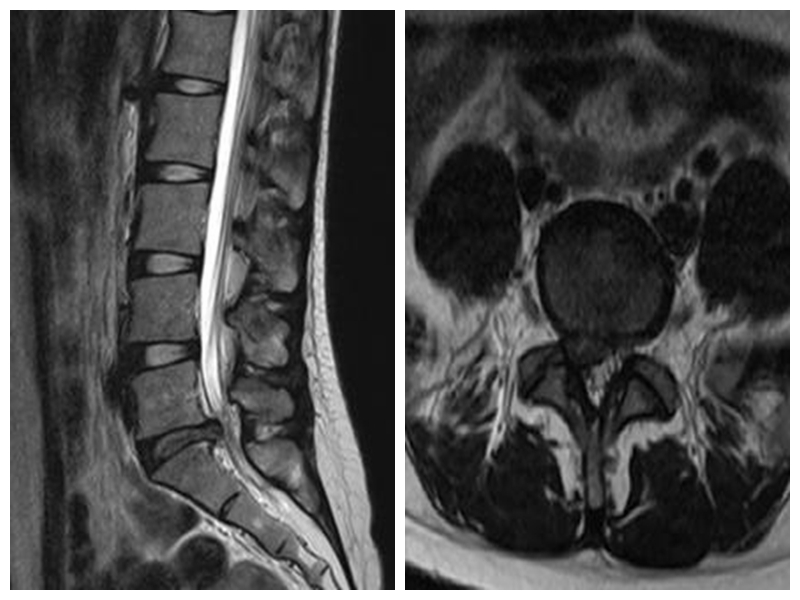

微創(chuàng)通道下椎間盤摘除、椎間植骨融合內(nèi)固定術(shù)

此項(xiàng)技術(shù)手術(shù)切口小,創(chuàng)傷小,不需要廣泛剝離肌肉及軟組織。可進(jìn)行髓核摘除、神經(jīng)根減壓、椎管減壓及復(fù)位、椎弓根釘內(nèi)固定、椎間融合等操作。術(shù)后恢復(fù)快,第2-3天即可佩戴腰圍下地行走。平均住院時(shí)間短,并發(fā)癥少,適應(yīng)癥廣泛,可應(yīng)用于治療腰椎間盤突出癥、腰椎失穩(wěn)、椎管狹窄癥及輕度的腰椎滑脫等疾病。

手術(shù)切口小,創(chuàng)傷小

典型病例:患者**,女,24歲,因“腰痛5年余,加重伴右下肢疼痛活動(dòng)受限1天”平車入院。PE:右下肢直腿抬高試驗(yàn)10°(+),右側(cè)踝反射消失,右下肢脛前肌、小腿三頭肌肌力4級(jí),右砪長伸肌力4級(jí),左下肢肌力5級(jí)。右臀部、右大腿后側(cè)針刺有麻木感,鞍區(qū)皮膚感覺正常。

本例患者術(shù)后3天在腰圍保護(hù)下獨(dú)立下地行走,腰痛及右下肢麻痛明顯緩解。